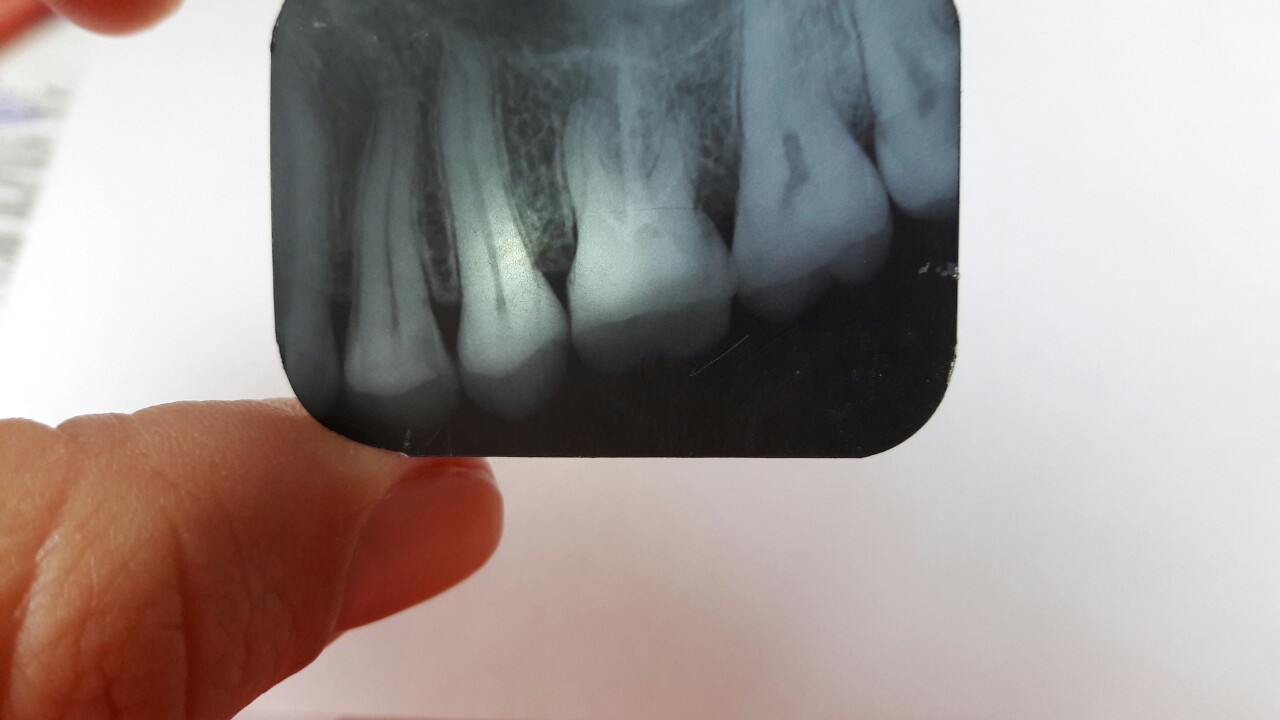

Добрый день, делала зуб, шестерку, начал болеть через 2 недели. Боль была очень сильная, у моего доктора смена закончилась, пошла к другому. После осмотра выяснилось, что воспалилась восьмерка, это она давала боль, отправили на удаление, но перед этим на рентген и восьмерки и на всякий случай и шестерки. И тут выяснилось что шестерку нужно переделывать, сказали идти к доктору, который делал . Я попыталась сфоткать рентген, подскажите пожалуйста, что не так и стоит ли идти переделывать к этому врачу, может опять что-то не так сделает, боюсь чтобы зуб не развалился от такого лечения. Тем более за кариозную восьмерку он промолчал. Не знаю что делатьНажмите на изображение для увеличения

...некачественная пломбировка каналов...на медиально-щечном корне - гранулема, поэтому шестой зуб вполне мог болеть из-за обострения хронического воспаления на корне... К слову, в этом зубе в 95% четыре канала, и четвертый канал, как раз в указанном корне...